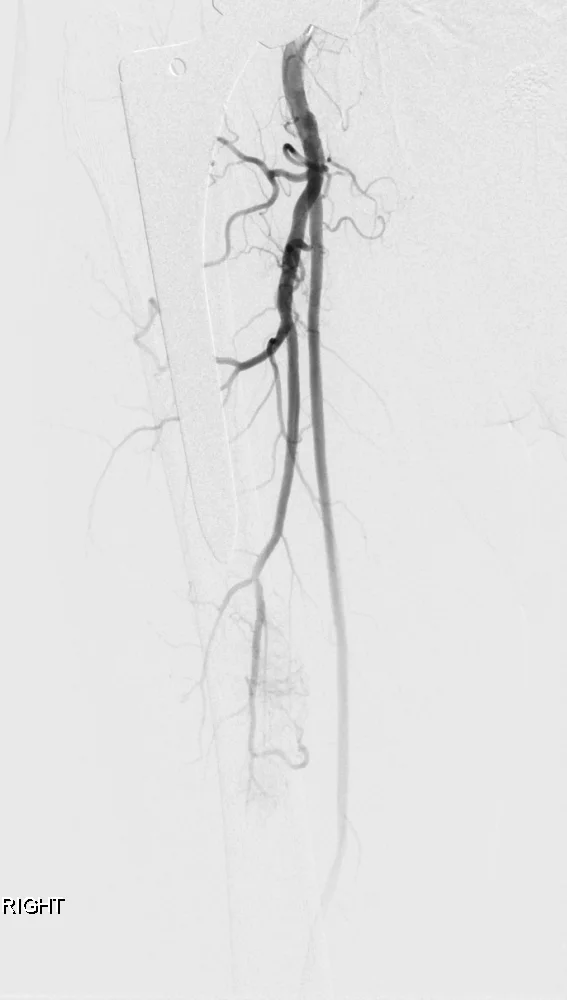

Preoperative Embolization: Case 1

72 year old patient with renal cell CA metastatic to bone presents for preoperative embolization prior to surgery.